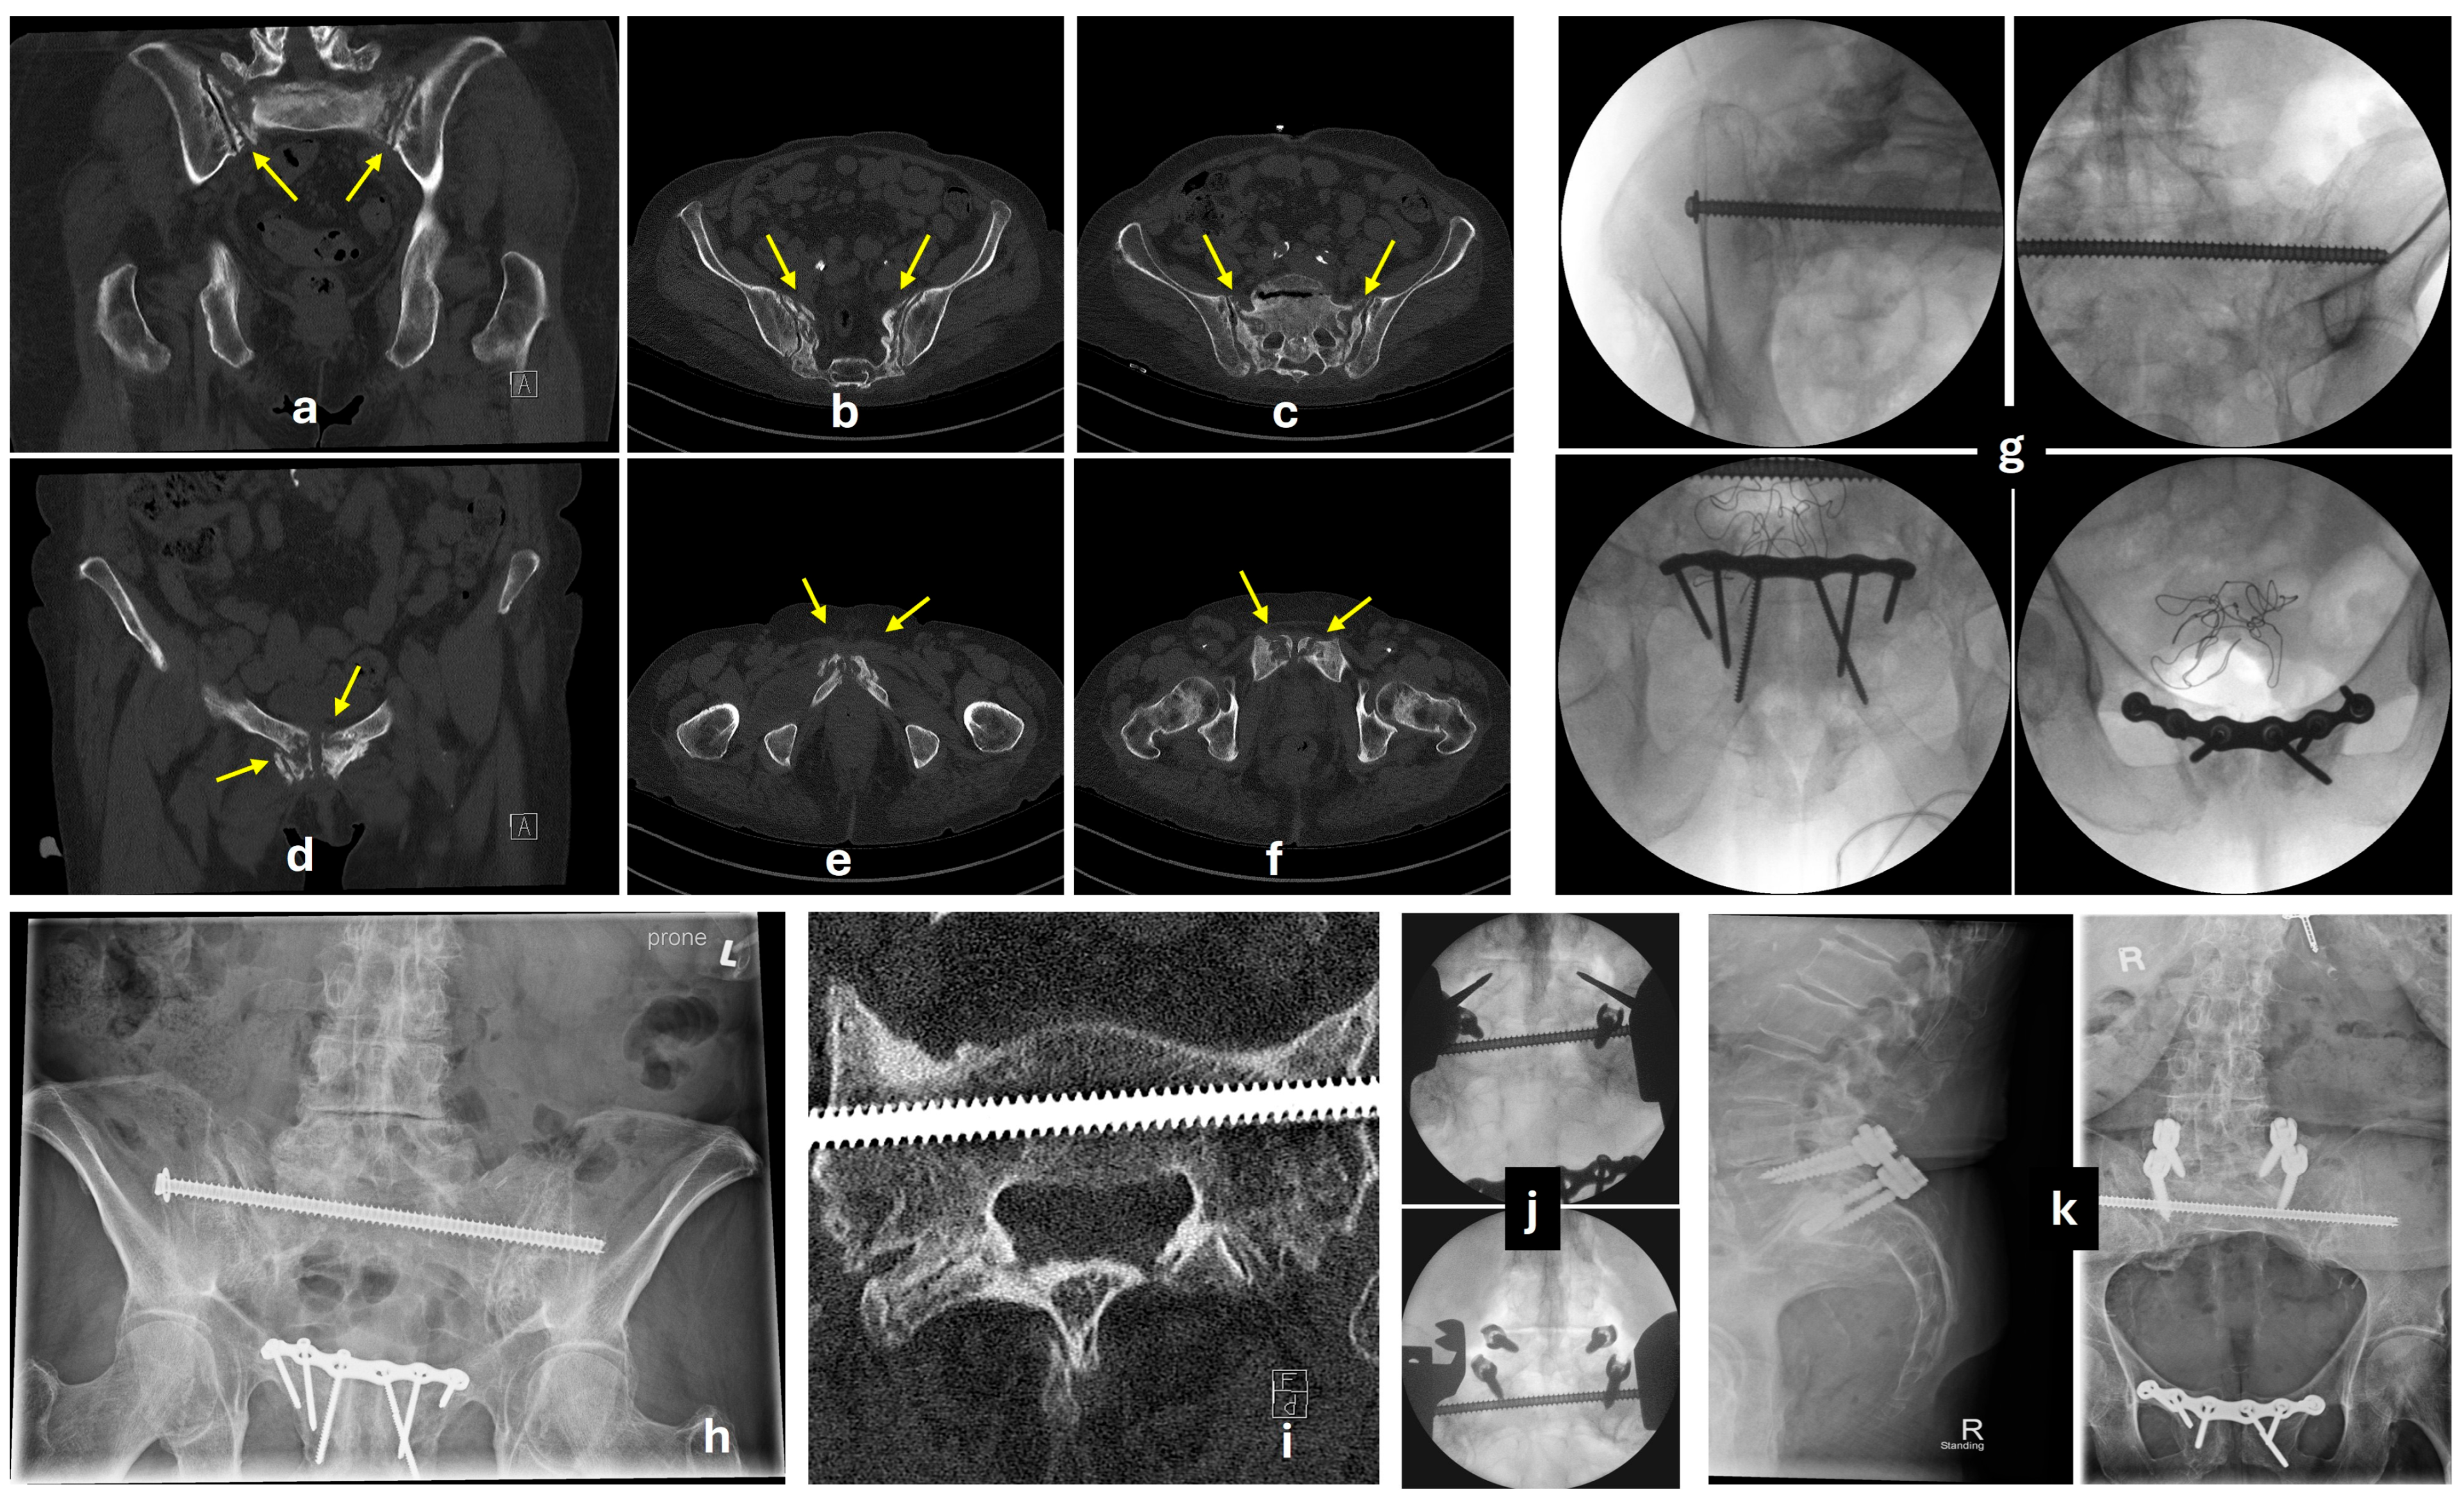

5.3. Posterior Fixation

5.3.1. Transiliac-Transsacral Screws

5.3.2. Transiliac Bridge Plating

5.3.3. Lumbopelvic Fixation

5.4. Anterior Fixation

5.4.1. Conventional Anterior Plating

5.4.2. Percutaneous Screw Fixation

5.4.3. External Fixator

5.5. Augmentation Techniques